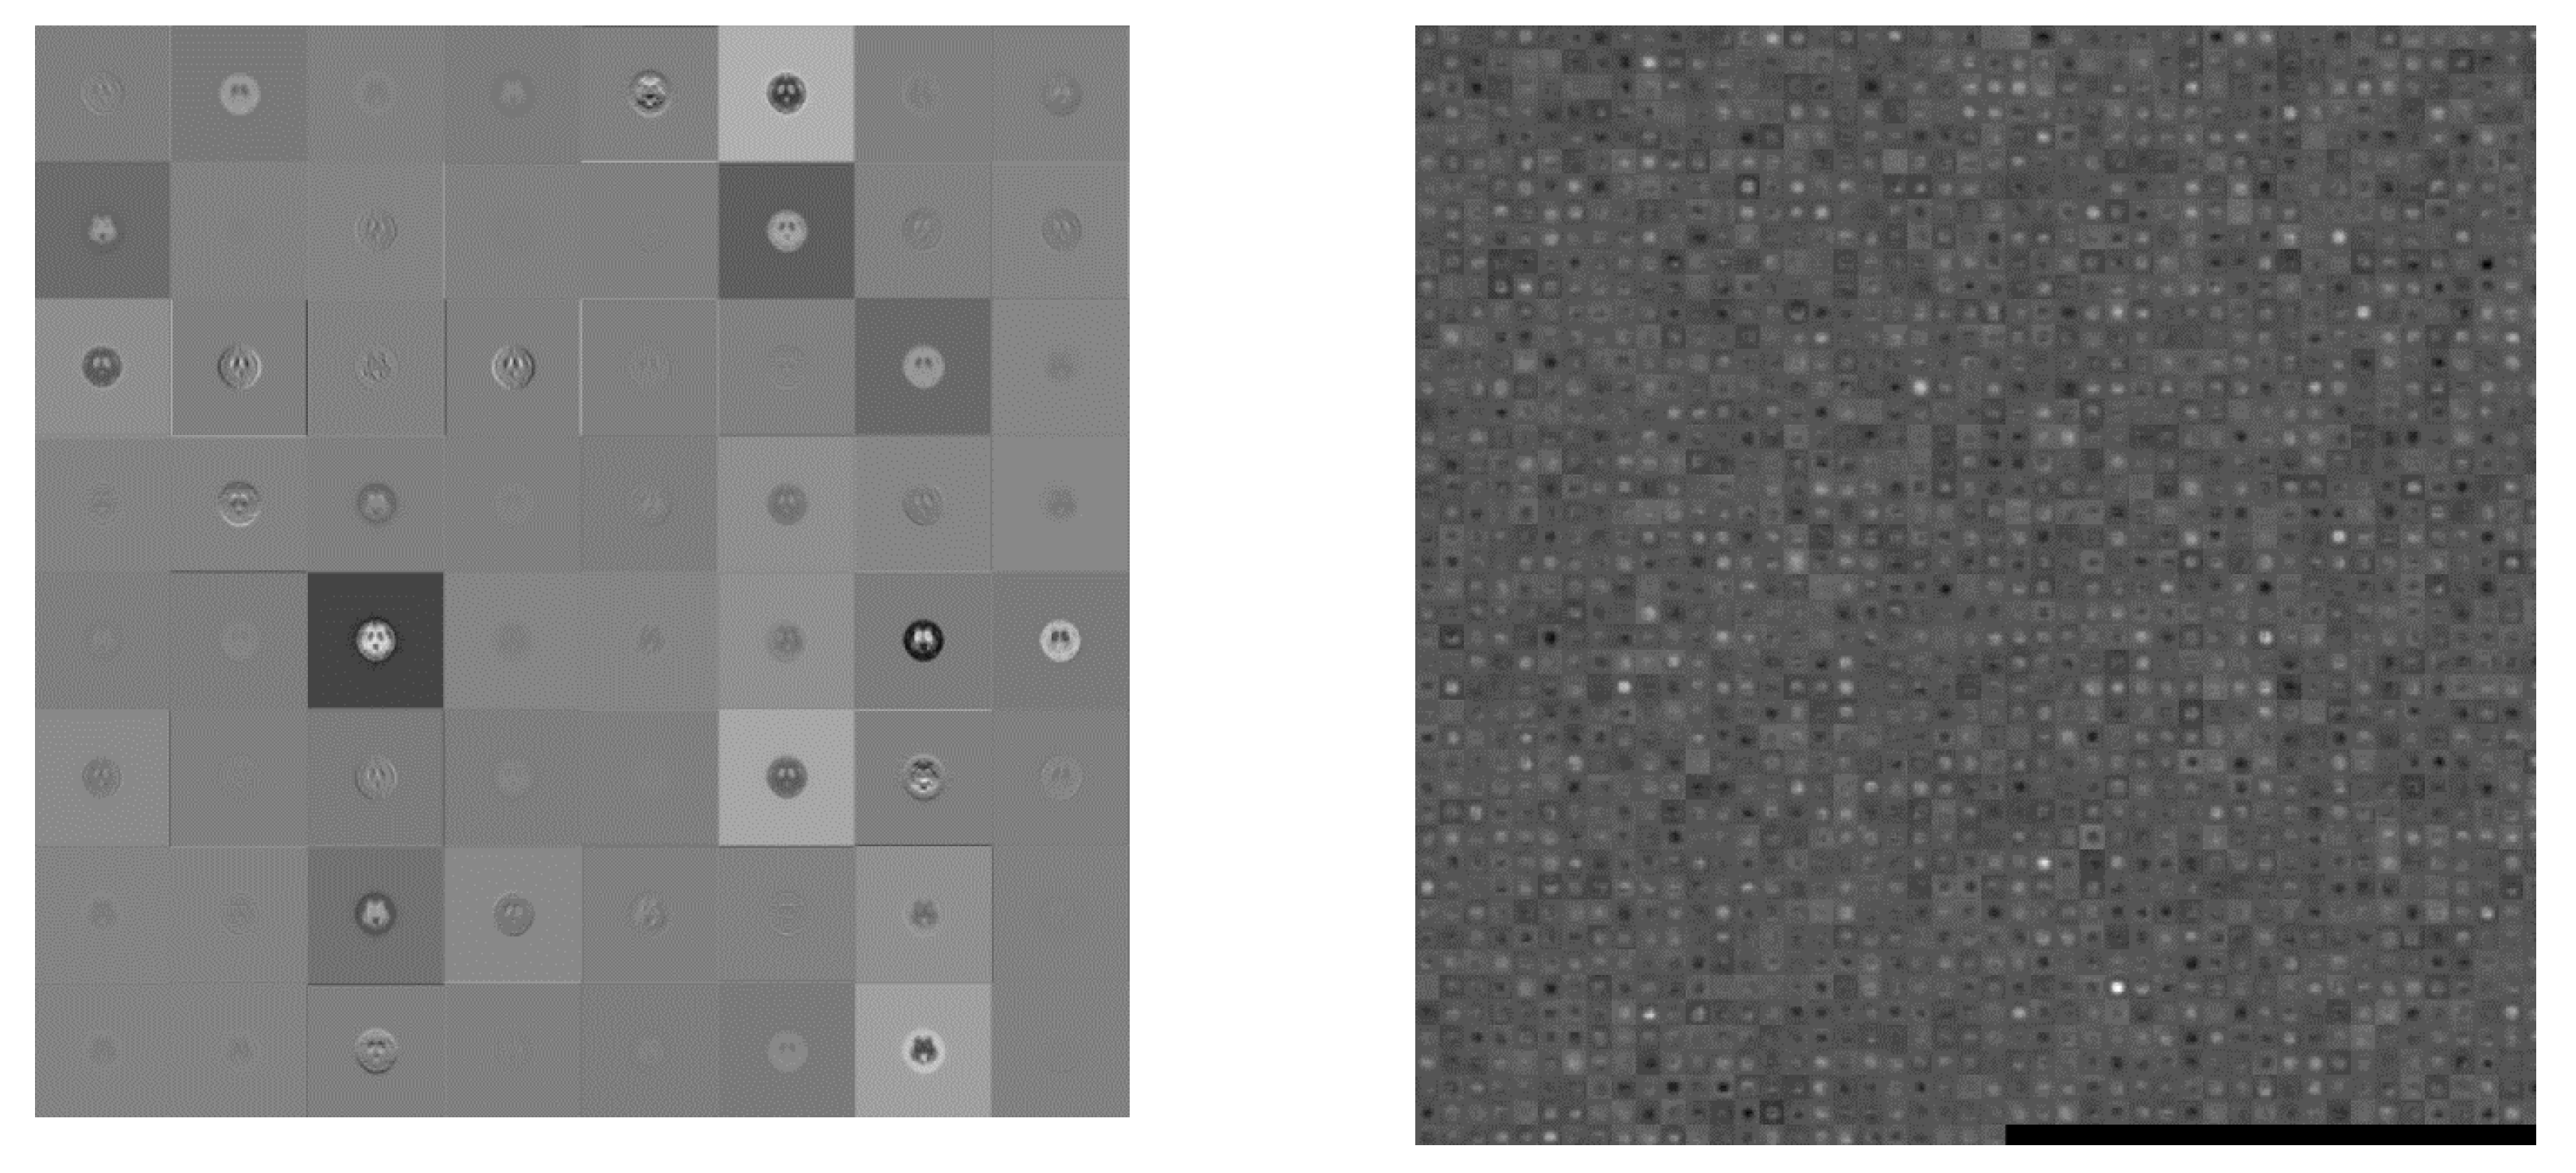

2.4. Popular Pre-trained Models in CNN

2.4.1. AlexNet